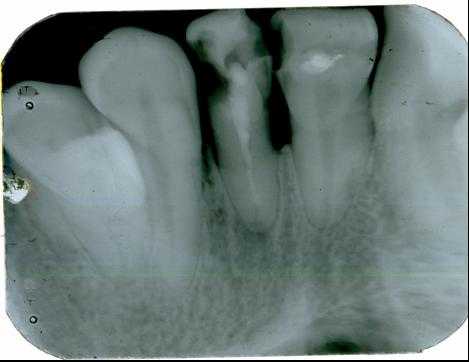

1. Внутриротовая контактная рентгенография

Основой рентгенологического исследования при большинстве заболеваний зубов и пародонта по-прежнему служит внутриротовая рентгенография.

Выполняется на специальном дентальном рентгеновском аппарате (хотя может быть выполнена и на обычном).

Для внутриротовой рентгенографии используют пакетированную или специально нарезанную (3x4 см) пленку, упакованную в светонепроницаемые стандартные пакеты.

На одном снимке можно получить изображение не более 2-3 зубов